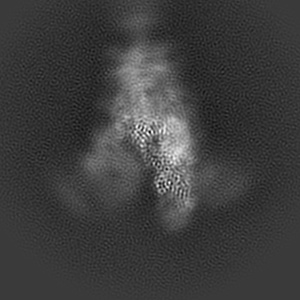

XBB-4 Fab in complex with SARS-CoV-2 BA.2.12.1 Spike Glycoprotein

Single-particle3.41 Å

Sample: XBB-4 Fab in complex with SARS-COV-2 BA.2.12.1 Spike Glycoprotein